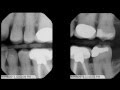

This dentist on Reddit who apparently had some free time decided to analyze the teeth of each of the 2016 democratic presidential candidates to see what kind of dental work they've undergone in the past. Hillary Clinton didn't fair so well with a couple crowns on her front teeth, but that's nothing compared to the work Joe Biden has done with pretty much all of his front teeth being crowns. Of course Obama's teeth are all perfect, and Bernie Sanders had a bit of work done too.